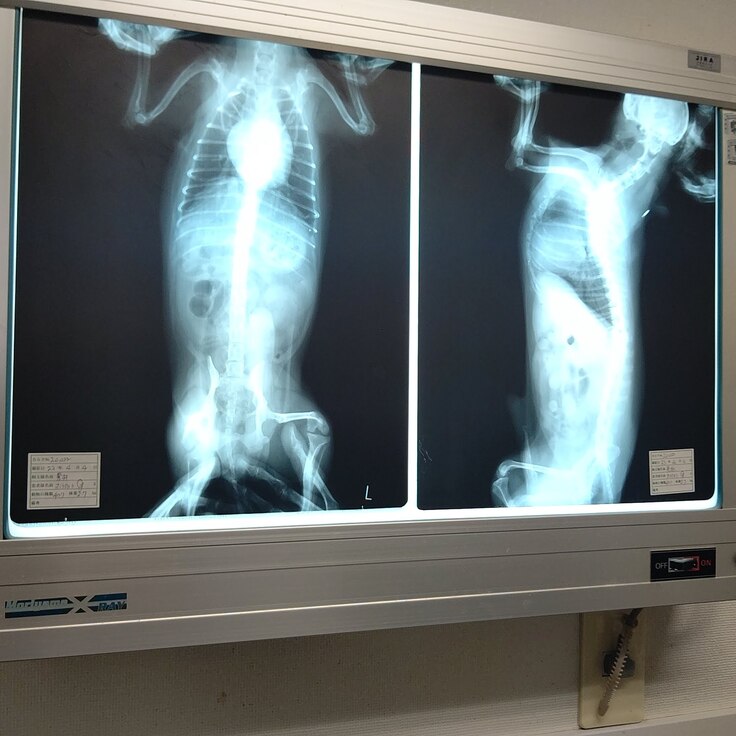

肺水腫...肺に水は溜まっていない

結果、心臓が大きくなって来ている為、心臓が気管を圧迫し、咳が出ているそうです